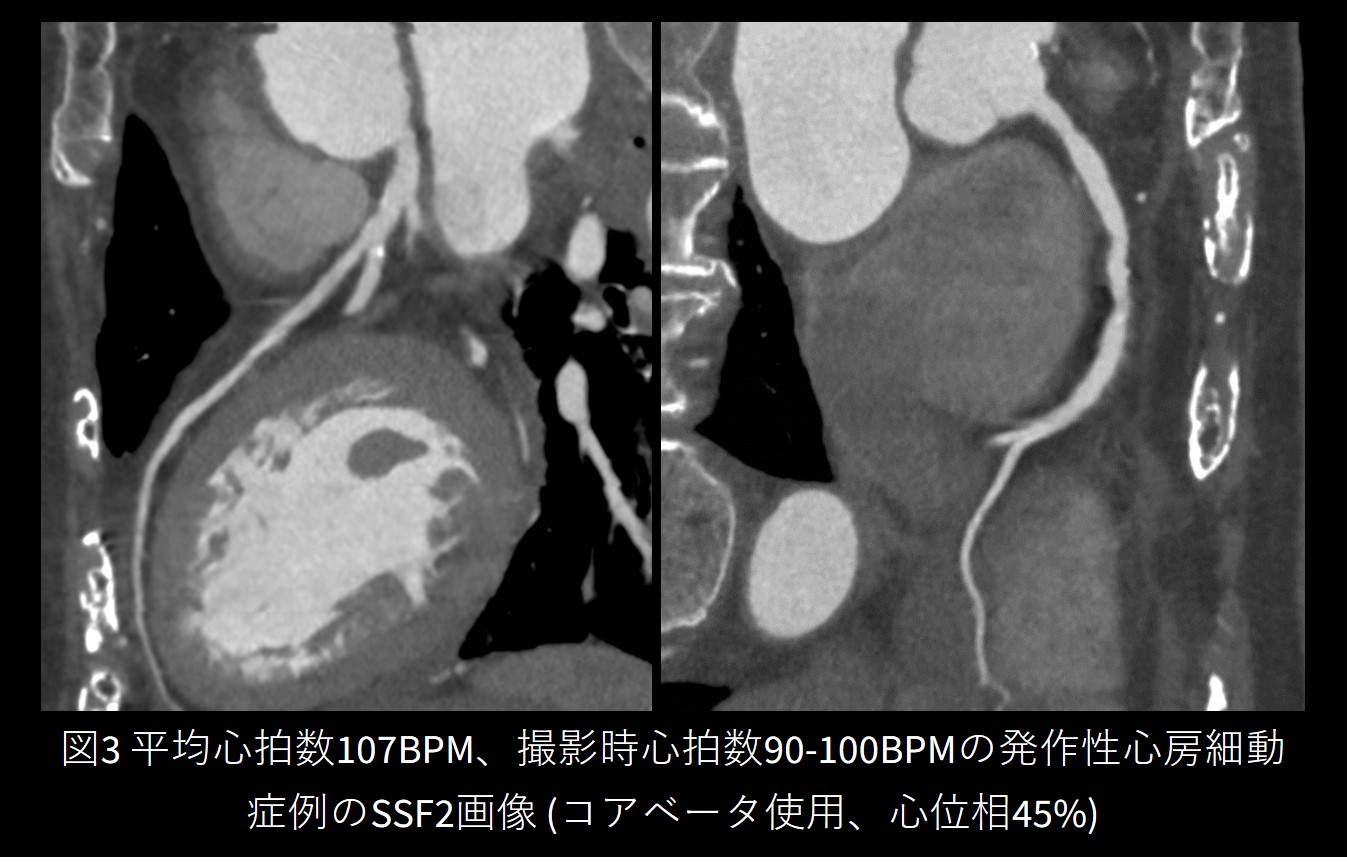

CTと同時に導入したSnapshot Freeze2.0 (以下SSF2) は、ワークステーション上のソフトウェアであり、心臓のモーションを補正し静止画像を作成する後処理機構です。撮影したCTデータから、3つの心位相での画像再構成を行い、ボクセル動態追跡によって各構造物の移動量を推定することで静止画像を得ます。

当院のワークフローでは、撮影後に自動で元データを作成・転送するように設定しているため、検査完了から10分程度でモーション補正済みの画像が得られるようになっています。SSF2によって高心拍をはじめ、以降に紹介する不整脈などの困難症例でも静止画像を提出することができています。

Frontier_Kofukyoritsu03.jpg

図2 SnapShot Freeze 2.0

Frontier_Kofukyoritsu04.jpg